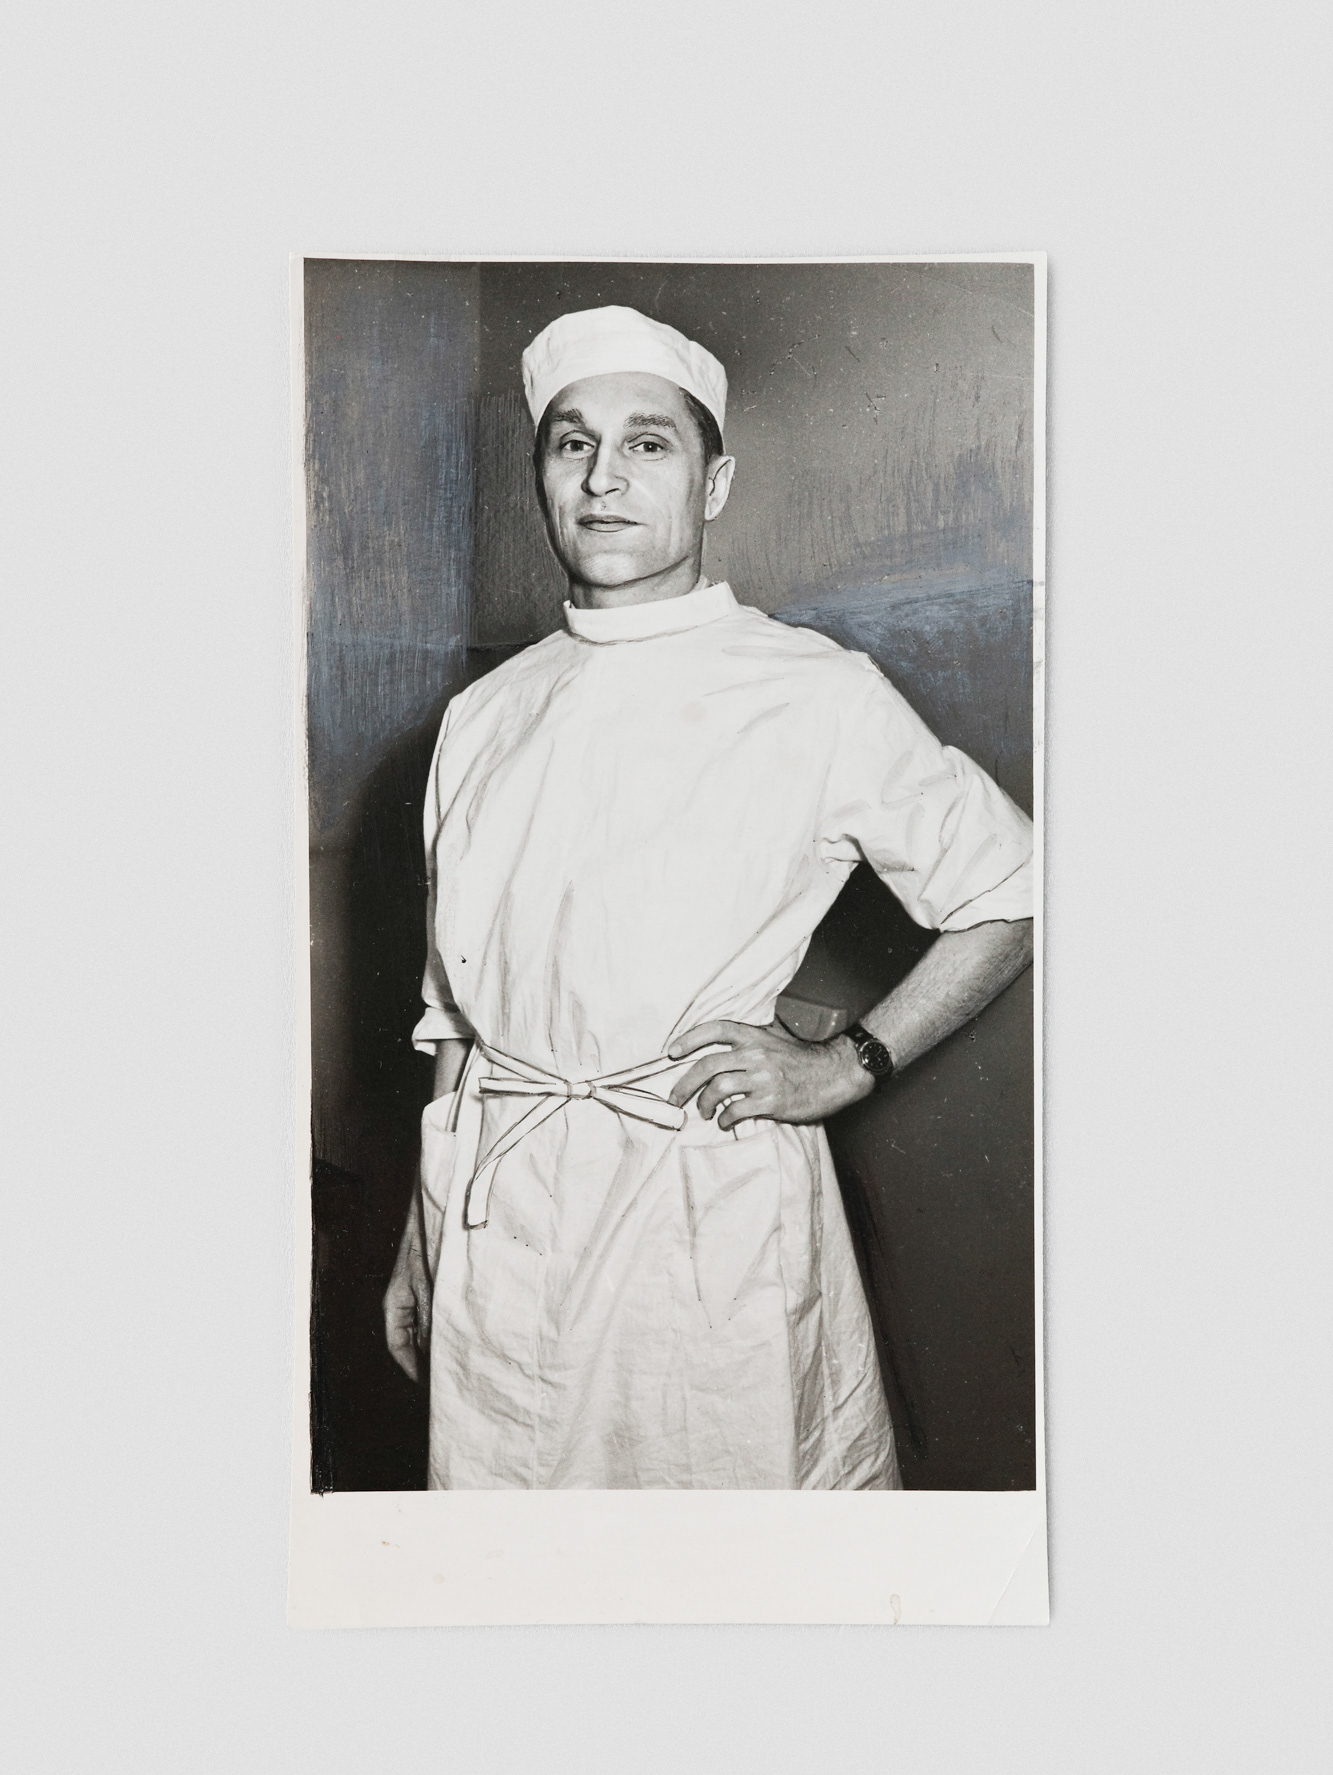

Chornobyl